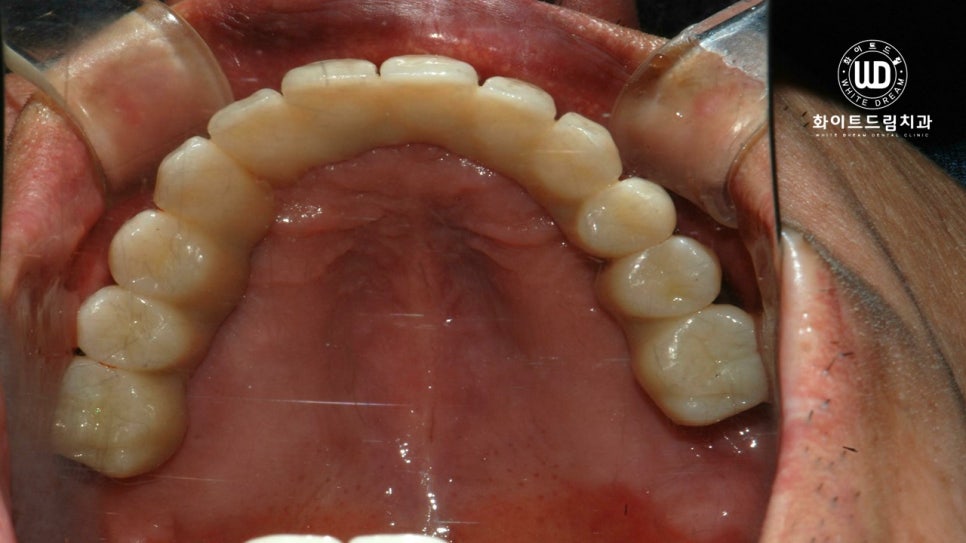

마지막으로, 하악 잔존 치아 2개 발치 후, 상하 전체 치조골 이식을 동반한 임플란트 식립 후 최종 진단 결과물입니다.

심미적, 기능적으로 주변 치아와 자연스럽게, 그리고 나이에 어울리도록 임플란트 시술이 마무리 된 것을 확인할 수 있었습니다.

뼈이식과 임플란트 식립에 있어서 가장 중요한 포인트는 바로 고정력 입니다. 임플란트를 여러개 식립하여 보철치료를 진행할 때, 저작하는 위치가 변하지 않고 모든 치아가 긴밀하게 위치할 수 있도록 교합 조절을 해드리는 것이 중요합니다.